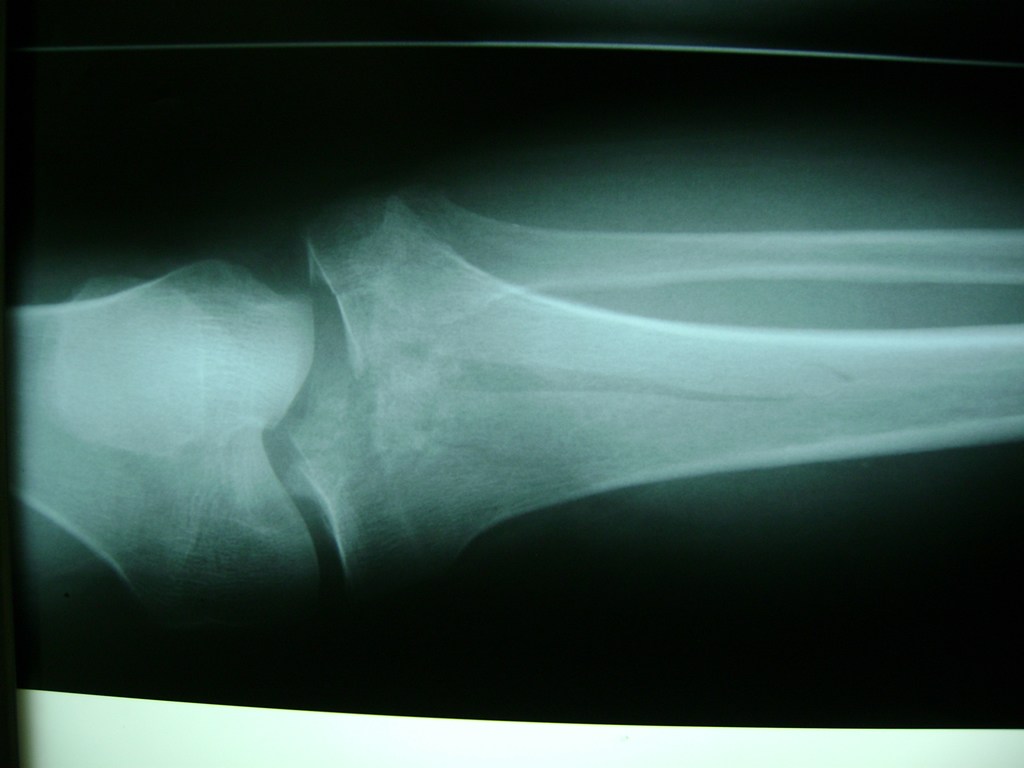

Cirugías de Rodillas

La artroscopia de rodilla es un cirugía en el cual la estructura interna de la articulación es examinada ya sea para realizar un diagnostico o para realizar un tratamiento, este procedimiento se realiza utilizando un instrumento parecido a un pequeño tubo llamado artroscopio.